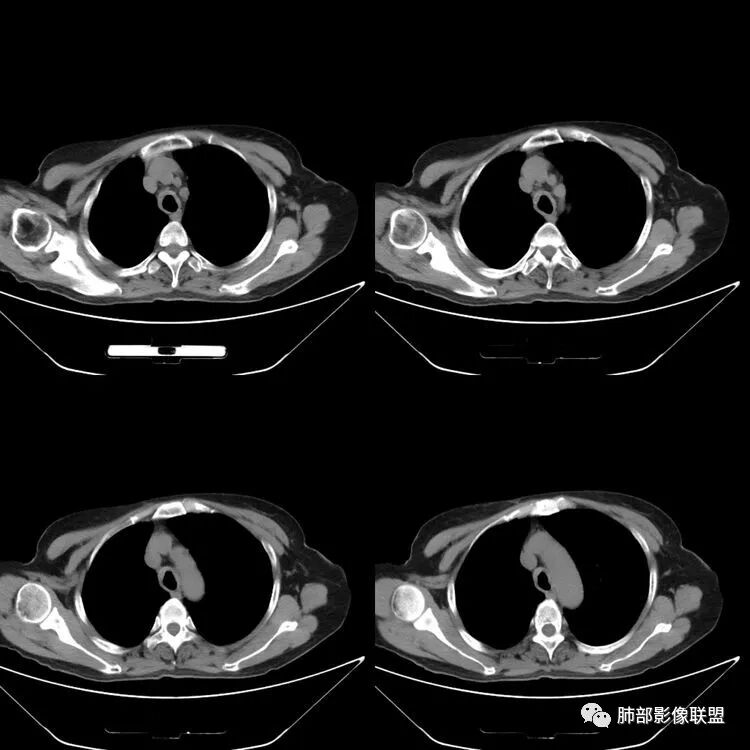

患者,女,64岁,反复咳嗽、咳痰、胸闷10年,加重2周患者10余年来每当受凉感冒出现咳嗽、咳痰、胸闷,有时痰中带血,输液治疗(具体不详)可好转。既往有声带肥厚手术病史。CT示气管、主支气管及分支支气管管壁弥漫性增厚累及膜部,局部伴钙化,管腔狭窄,考虑淀粉样变性

患者,女,64岁,反复咳嗽、咳痰、胸闷10年,加重2周。气管支气管及两肺下叶 支气管弥漫性的环状增厚,管腔扩张,管腔感觉比较松弛。第一感觉,气管支气管淀粉样变。鉴别诊断,1、支气管内膜结核,肺内散在一些支气管的播散病灶,粟粒结节为主,形态比较单一。2、复发性的多软骨炎,就得了解一下其他部位,有没有多个部位的软骨炎。这个病人右侧胸廓缩小,升主动脉明显的扩张,其横径明显的超过了降主动脉。

征象很明确

弥漫支气管壁增厚,膜部受累

南边:肺部有肺气肿支气管腔狭窄淀粉样变性?复发性多软骨炎?血管炎?慢支?结核?曲霉菌?南边:一般还是淀粉样变性与复发性多软骨炎鉴别其次就是支气管骨化症,但是骨化下朝上,且壁结节状钙化明显,本例不太支持。至于结核、曲霉菌?1.结核,一般不会这么广泛,支气管壁狭窄后扩张2.曲霉菌可以这么广泛,但是支气管壁管腔扩张,而且附近脂肪间隙有炎性反应,不太支持;3.血管炎,一般合并肺内有病灶,但是声带受累,放待排;4.软骨炎一般全身受累,例如耳廓等;而且膜部不受累,不太支持;倾向于淀粉样变性;淀粉分很多型,气管支气管是最常见的。尘缘:影像上生理性钙化与支气管骨化无法区别,镜检也不好鉴别,需要依赖活检,看粘膜中是否合并炎性改变(淋巴细胞,组织细胞等炎性细胞侵润)来鉴别Coke with ice:经常看到的这种是老年性肺改变,又称年龄相关肺改变。气管和支气管弥漫性软骨钙化,常见老年女性。尘缘:支气管骨化症很罕见的,所以绝大多数还是生理性钙化。对于老年人,无临床症状的钙化,还是基本上都是生理性钙化,无临床意义。大雄:如果管壁钙化伴明显增厚 影像还是提示一下建议支气管镜稳妥些

病理结果:肺淀粉样变

气管支气管淀粉样变性

三、影像表现

1.气管支气管型

①气管支气管壁增厚,形成粘膜下斑块与结节

②管腔广泛狭窄、闭塞

③管壁钙化

④膜部受累(具有重要鉴别意义)